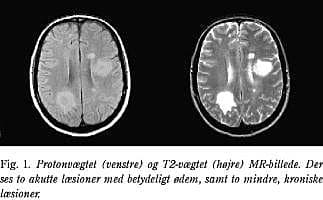

FLAIR

Ved FLAIR (fluid-attenuated inversion recovery) undertrykkes signalet fra CSF, hvilket letter visualiseringen af læsioner på overgangen mellem CSF og hjerne (Fig. 3). Kortikale, subkortikale og periventrikulære læsioner samt læsioner svarende til corpus callosum ses således tydeligere (3, 6). Desværre er FLAIR-sekvenserne oftest mindre sensitive end T2-vægtede og protonvægtede billeder til påvisning af infratentorielle læsioner, hvorfor metoden ikke rutinemæssigt bør anvendes alene (3).